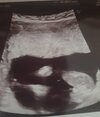

Hej dziewczyny jestem po wizycie usg polowkowym 19 tydz .. No i lekarza wypowiedz Prawdopodobnie dziewczyna bedzie bo,, nic tu nie dynda,, ale nie mowi ze nie wyjdzie z tego chlopiec tylko na dzien dzisiejszy powinno na chlopcaa cos dyndac miedy nogami tu nie dynda więc wniosek ze bedzie chyba Martynka 🤷🏼‍♀😁 co myslicie?